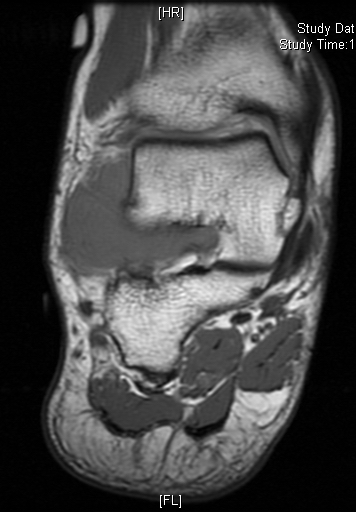

MRI

Shows multiloculated, heterogeneous mass.

“Triple Signal Intensity sign”; hypointense, isointense and hyperintense with fat on T2 – weighted MRI imaging. This sign is present in 30 to 50% of the cases. (Fig.3)

Under contrast enhancement Synovial Sarcoma appears heterogeneous and demonstrate areas of nodular enhancement.

In approximately 30% of cases a multiple vascular cannel may be identified

Synovial sarcomas may have a cystic appearance and are often mistaken for ganglion cysts especially those adjacent to tendons and in the foot and ankle.